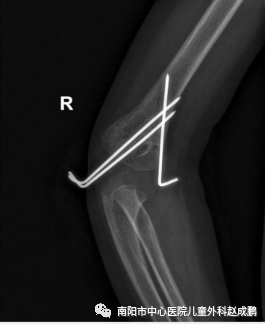

vsd引流器怎么连接创面负压封闭引流技术(VSD),让患者创面更快痊愈!_https://www.jmylbn.com_新闻资讯_第10张

vsd引流器怎么连接创面负压封闭引流技术(VSD),让患者创面更快痊愈!_https://www.jmylbn.com_新闻资讯_第11张

骨折闭合复位经皮穿针固定(不切开)术前、术后